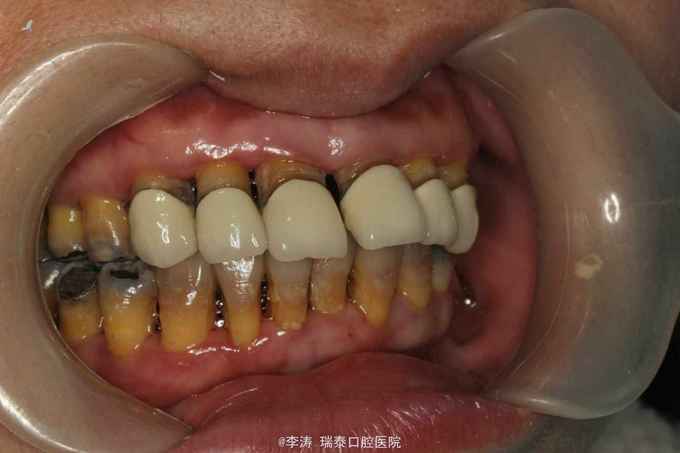

前牙烤瓷冠修复十年,现牙根暴露影响美观求治

13到24烤瓷冠修复,牙根暴露约3mm,黑三角明显,中位笑线,前牙松动不明显。 X线片11,12,13均吸收至根尖三分之一,21,22,23,24约根中三分之一,根尖未见明显暗影